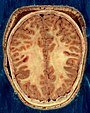

Исследование наполнено ошеломляющей статистикой. Чтобы получить изображение человеческого мозга, исследователям пришлось использовать технологию машинного обучения Google, что позволило сократить время завершения проекта на несколько лет. Сначала ученые разрезали образец на 5000 пластин, тоньше человеческого волоса. С каждого среза были сделаны электронные микроскопические изображения, которые были рекомбинированы, чтобы насчитать около 50 000 клеток и 150 миллионов синапсов — точек соединения, где нейроны встречаются и взаимодействуют. Чтобы рекомбинировать эти изображения и точно составить карту волокон и клеток, пришлось использовать технологию искусственного интеллекта Google, которая в цифровом виде определяла маршруты серого вещества.

Синтезированные изображения раскрыли множество захватывающих тайн мозга, которые ранее были совершенно неизвестны: некоторые кластеры клеток росли как зеркальные изображения друг друга. У одного нейрона было обнаружено более 5000 точек соединения с другими нейронами, а некоторые аксоны (концы нервов, передающие сигналы) по совершенно неизвестным причинам плотно свернулись в клубок. Эти и другие открытия, сделанные в ходе исследований, взбудоражили ученых сверх всякой меры. Джефф Лихтман, профессор Гарварда, рассказал The Guardian о проекте: «В этом наборе данных мы обнаружили много вещей, которых нет в учебниках. Мы не понимаем этих вещей, но я могу вам сказать, что они находятся между тем, что мы уже знаем и тем, что нам нужно знать».

Чтобы понять размер образца мозга и собранных из него данных, нам нужно разобраться с ошеломляюще колоссальными цифрами. Кубический миллиметр мозгового вещества составляет лишь одну миллионную часть размера мозга взрослого человека, однако сканированные изображения и полная карта его сложностей составляют 1,4 петабайта или 1,4 миллиона гигабайт. Если бы сегодня кто-то использовал подход Google/Гарварда для картирования всего человеческого мозга, сканы заняли бы 1,6 зеттабайт памяти.